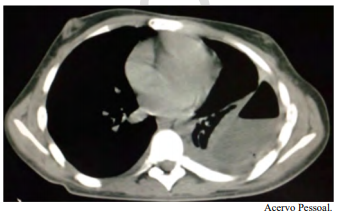

O mais provável fator de risco para a condição que o paciente apresenta é exposição ao asbesto e ao tabaco.